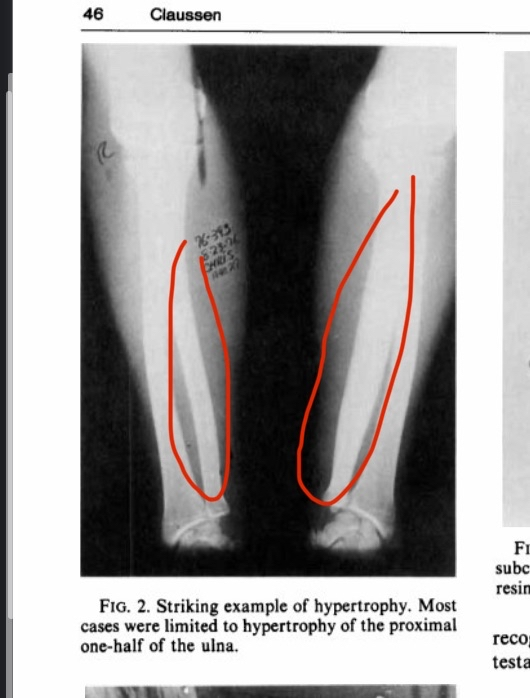

This study examined professional bareback rodeo riders (without a saddle), showing extreme bone hypertrophy in the ulna. The hypertrophy results from direct trauma and impact with the hip bone. For perspective, some individuals had up to a 92% increase in bone diameter and a 268% increase in cross-sectional area, which is extremely unusual. The image in the study shows significant hypertrophy, though not the individual with nearly doubled bone diameter.

If anyone claims this hypertrophy is caused by muscle pull alone, that is incorrect. The main reason is direct trauma to the bone, supported by the following:

- Many other sports generate high torsional forces on the bone, but hypertrophy does not exceed 10% compared to rodeo riders, indicating torsion alone cannot explain the extreme growth. Direct trauma plays a key role.

- The hypertrophy occurs only in the area where the humerus contacts the hip bone, exactly at the point of contact and impact. This localized growth confirms direct pressure and trauma are the main causes.

- Hypertrophy was observed only in riders without a saddle, where the humerus presses directly against the hip. Saddles act as a barrier that reduces direct pressure and trauma, preventing bone growth.

- The large variation in hypertrophy between individuals is due to some using protective pads that reduce trauma, while others did not. This shows how protection affects trauma and the extent of hypertrophy.

- Significant hypertrophy is seen in bareback riders, but not in saddle riders, further supporting that direct trauma and impact are the main drivers of bone growth.